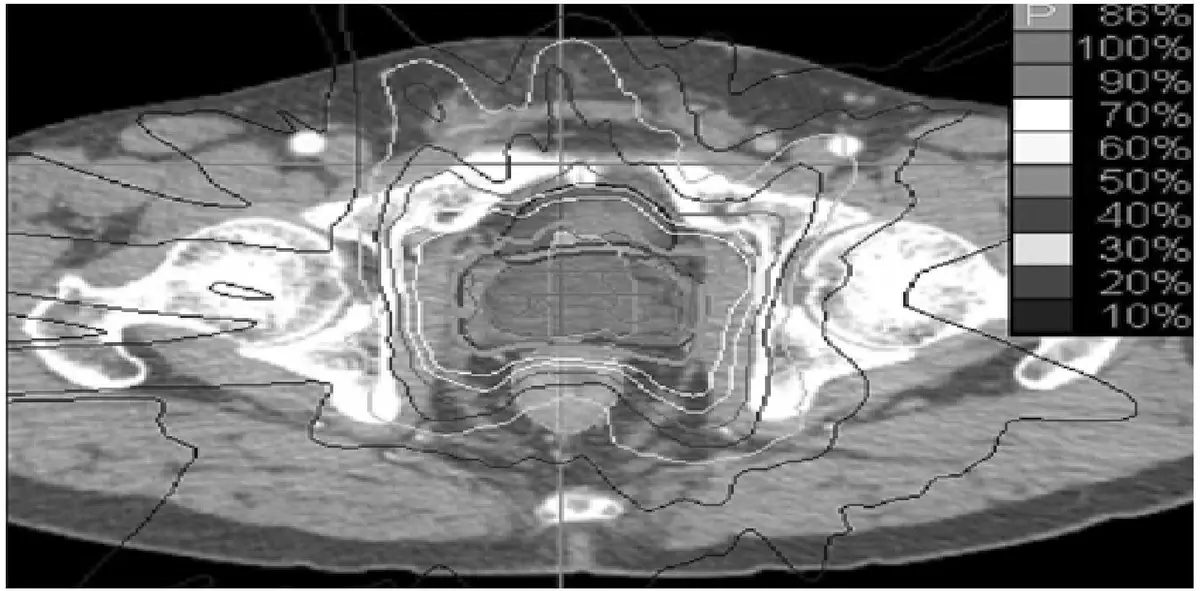

圖片顯示攝護腺位置的骨盆腔軸位(axial)CT 治療計畫影像,疊加了等劑量線(isodose lines)分布(從 10% 至 100%)。影像中可清楚識別:

- 攝護腺(prostate):位於影像中央,接受最高劑量集中(100% 等劑量線包覆)

- 直腸(rectum):攝護腺正後方(影像下方),受高劑量線影響明顯,為最重要的 OAR

- 膀胱(bladder):攝護腺前方(影像上方),同樣受高劑量區涵蓋

- 雙側股骨頭(femoral heads):影像兩側的圓形高密度骨性結構,可見等劑量線延伸至此區域

- 脊髓(spinal cord):此骨盆切面上完全看不到脊髓,因為脊髓在解剖上位於腰椎以上,與攝護腺的解剖距離遠超出放射治療的劑量影響範圍